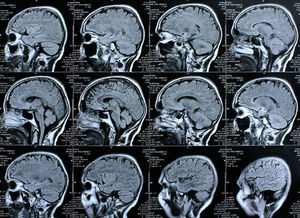

Gehirn-Scans: MRT zeigt Veränderungen deutlich auf. Bild: pixelio.de, Rike